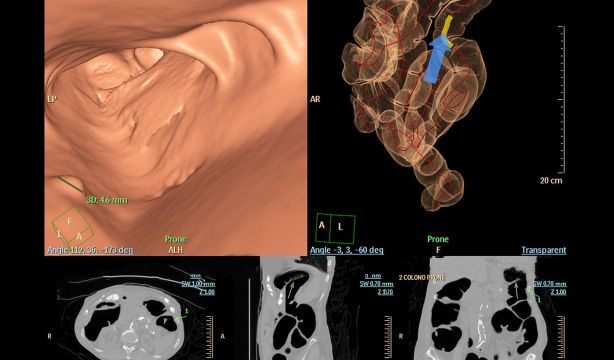

Y tenemos, además, "de la colonoscopia tradicional, la virtual. A diferencia de la primera, que requiere que se introduzca un endoscopio en el recto y se avance a través del colon, la virtual utiliza una tomografía computarizada para producir cientos de imágenes transversales de los órganos abdominales. Luego, las imágenes se combinan para proporcionar una vista completa del interior del colon y del recto. Para la colonoscopia virtual se requiere una limpieza intestinal similar a la de la colonoscopia habitual".

La prueba de ADN fecal multiobjetivo (mt-sDNA), que analiza muestras de heces en busca de biomarcadores específicos de cáncer colorrectal, y la colonoscopia Ct o virtual, que utiliza tomografías computarizadas para examinar el colon y el recto en busca de cáncer o pólipos, son ahora procedimientos cubiertos para los beneficiarios de Medicare.